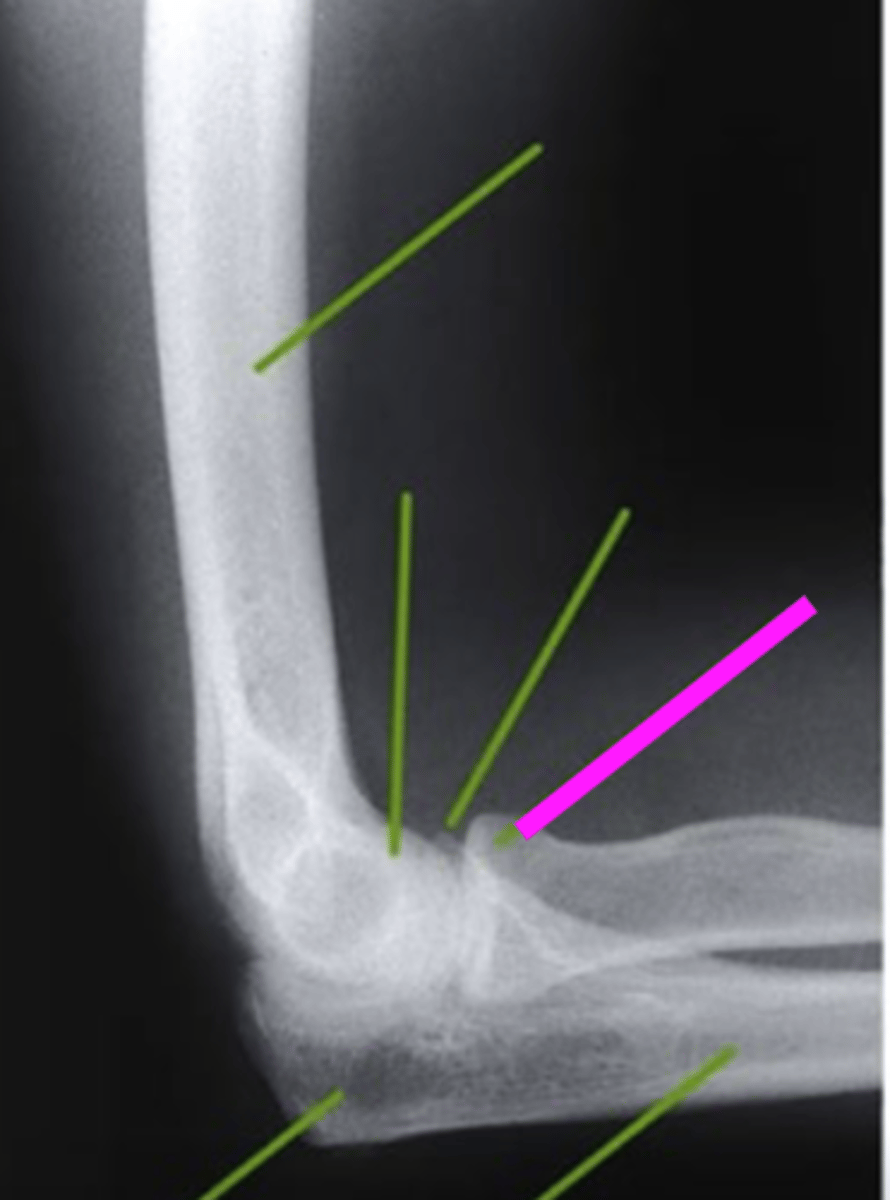

internal oblique elbow

what view is this

coronoid process

What does the blue line point to?

external oblique elbow

radial head

what does the green line point to?